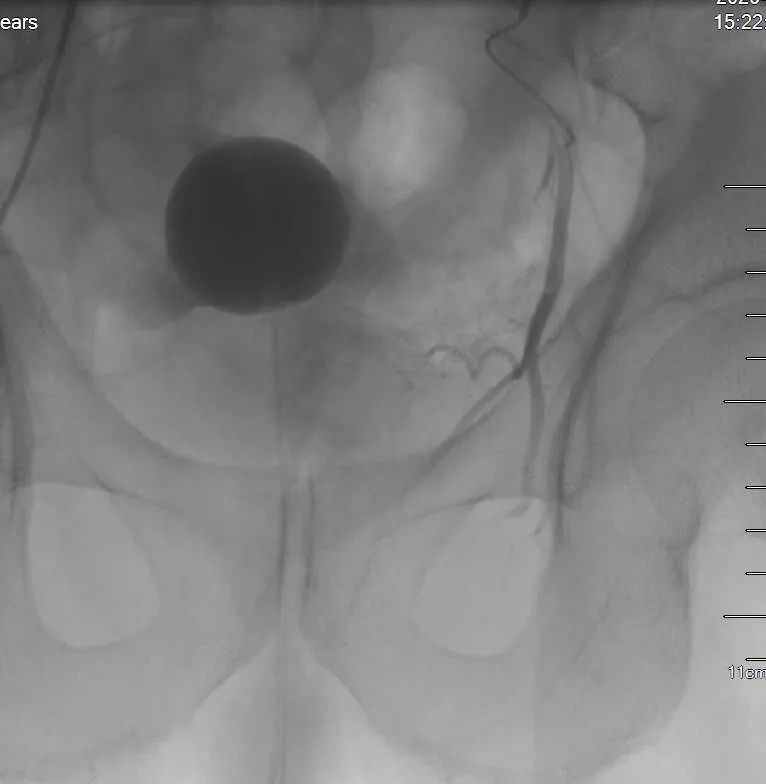

患者在局部麻醉下经股动脉穿刺,引入导管至前列腺的供血动脉,注入栓塞微粒,阻断前列腺腺体的血液供应,使增生的前列腺因缺血萎缩而体积缩小,解除对尿道的压迫及下尿路梗阻,使排尿恢复顺畅。一般栓塞治疗 3 天左右即可拔除导尿管,恢复正常排尿。介入栓塞治疗具有创伤小、痛苦少、并发症少、恢复快等优点,且术前、术后饮食正常,穿刺点压迫 2 小时~4 小时即可下床自由活动。值得临床推广应用。